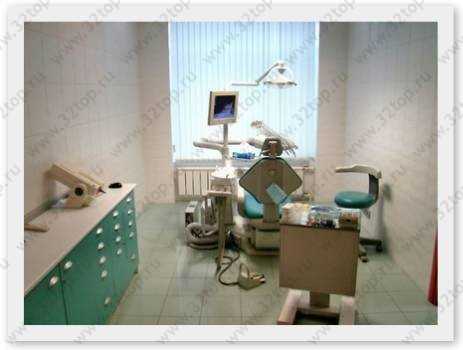

Стоматология NN DENT (НН ДЕНТ) м. Войковская

Стоматологии рядом с метро Войковская